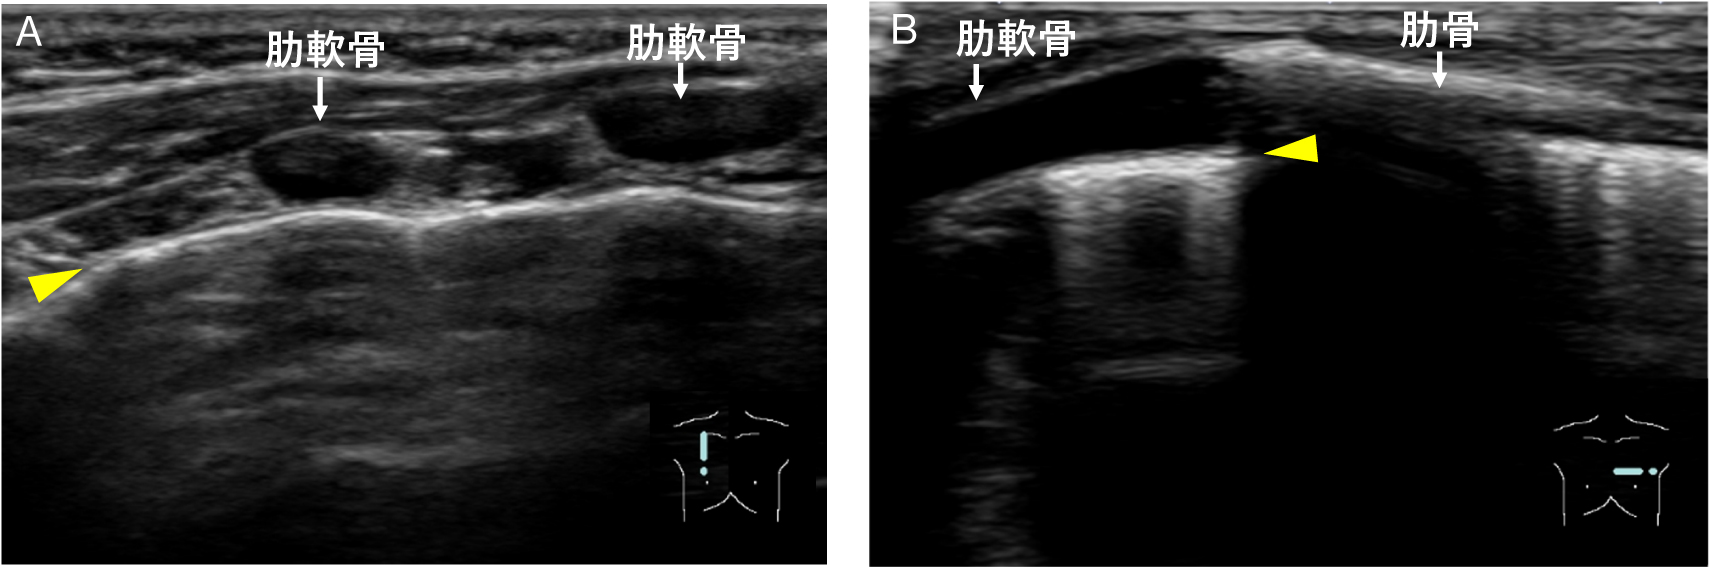

また,胸郭には肋骨と胸骨とを連結する肋軟骨が存在する(Fig.3)4).音響インピーダンスの大きい肋骨と異なり,肋軟骨は超音波を透過するため低~無エコーに描出され,音響陰影は伴わない.そのため,肋軟骨下は胸膜ラインが観察可能である(Fig.4).さらに小児の場合,低年齢であるほど骨化が未熟で軟骨成分が多いため,骨による音響陰影の影響を受けにくい反面,bat signの目印となる骨化した肋骨による音響陰影が生じない.そのため,小児呼吸器超音波検査を施行する場合は,超音波上の正常軟骨像を把握しておくことが肝要である.

胸郭には,肋骨と胸骨とを連結する肋軟骨が存在する.小児の場合,低年齢であればあるほど骨化が未熟であり,肋骨部分の軟骨成分が多い.

A:右傍胸骨部,肋軟骨に直行する断面

B:左傍胸骨部,肋軟骨に沿った断面

肋軟骨は超音波を透過するため低~無エコーに描出され,音響陰影は伴わない.そのため,肋軟骨下は胸膜ライン(黄色矢頭)が観察可能である.

*AとBは別症例.